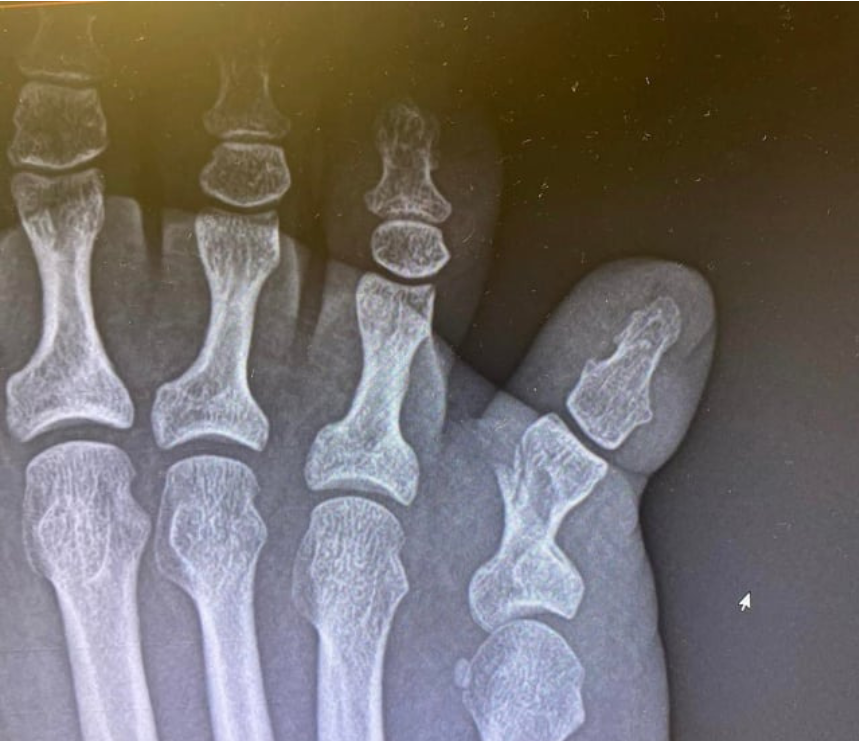

이 중 골절 진단비는 가장 기본적인 항목으로, 엑스레이나 CT를 통해 골절이 확인되면 지급됩니다. 다만 단순 금(금이 간 경우)과 완전 골절 여부에 따라 보험사에서 지급 기준을 다르게 적용하는 경우도 있습니다.

골절은 단순히 뼈가 부러졌다는 개념을 넘어서, 형태와 손상 정도에 따라 여러 유형으로 구분됩니다. 발가락 골절에서도 동일하게 적용되며, 치료 방식과 보험 처리에도 영향을 줍니다.

폐쇄성 골절은 피부 손상 없이 뼈만 부러진 상태를 의미합니다. 가장 흔한 형태이며, 대부분의 발가락 골절이 여기에 해당합니다.

- 특징: 피부 외부 손상 없음

- 감염 위험: 낮음

- 치료: 깁스, 보호대, 경우에 따라 수술

- 회복 기간: 약 3~6주